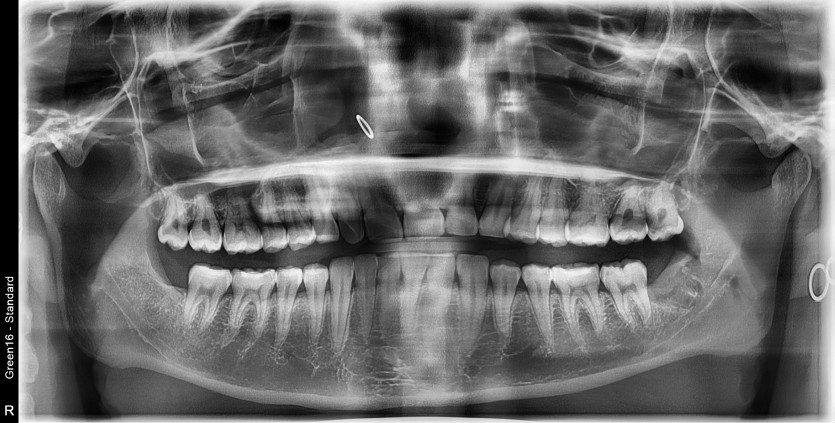

#38,48 사랑니 발치

구강 외과 전문의가 당일 발치했습니다.